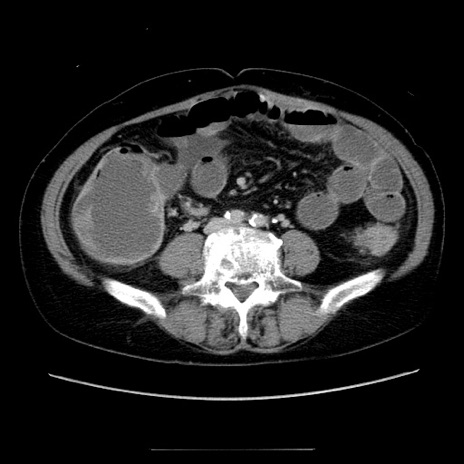

症例5(横断像)

【症例】70歳代女性

【主訴】お腹が張る

【現病歴】1週間くらい前から腹部膨満の自覚あり。昨日夜から増悪したため、本日救急外来受診。

【身体所見】意識清明、BT 36.5℃、BP 165/106mmHg、HR 80bpm、SpO2 98%、腹部:膨満、軟、自発痛・圧痛なし、触診にて不快感あり、腸蠕動音:減弱

【データ】WBC 12600、CRP 1.04